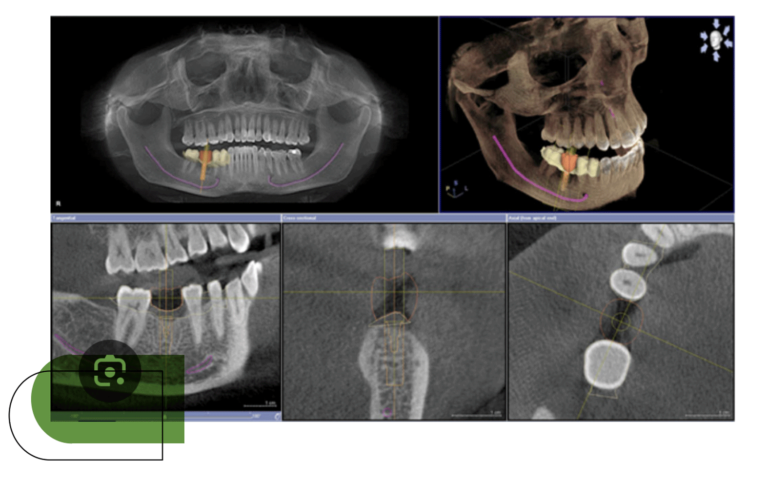

DIGITAL 3D SCANNING

Three-dimensional X-ray of the mouth that allows a precise diagnosis of bone structures and teeth, but also to measure and plan the placement of an implant with the help of a 3D surgical guide.